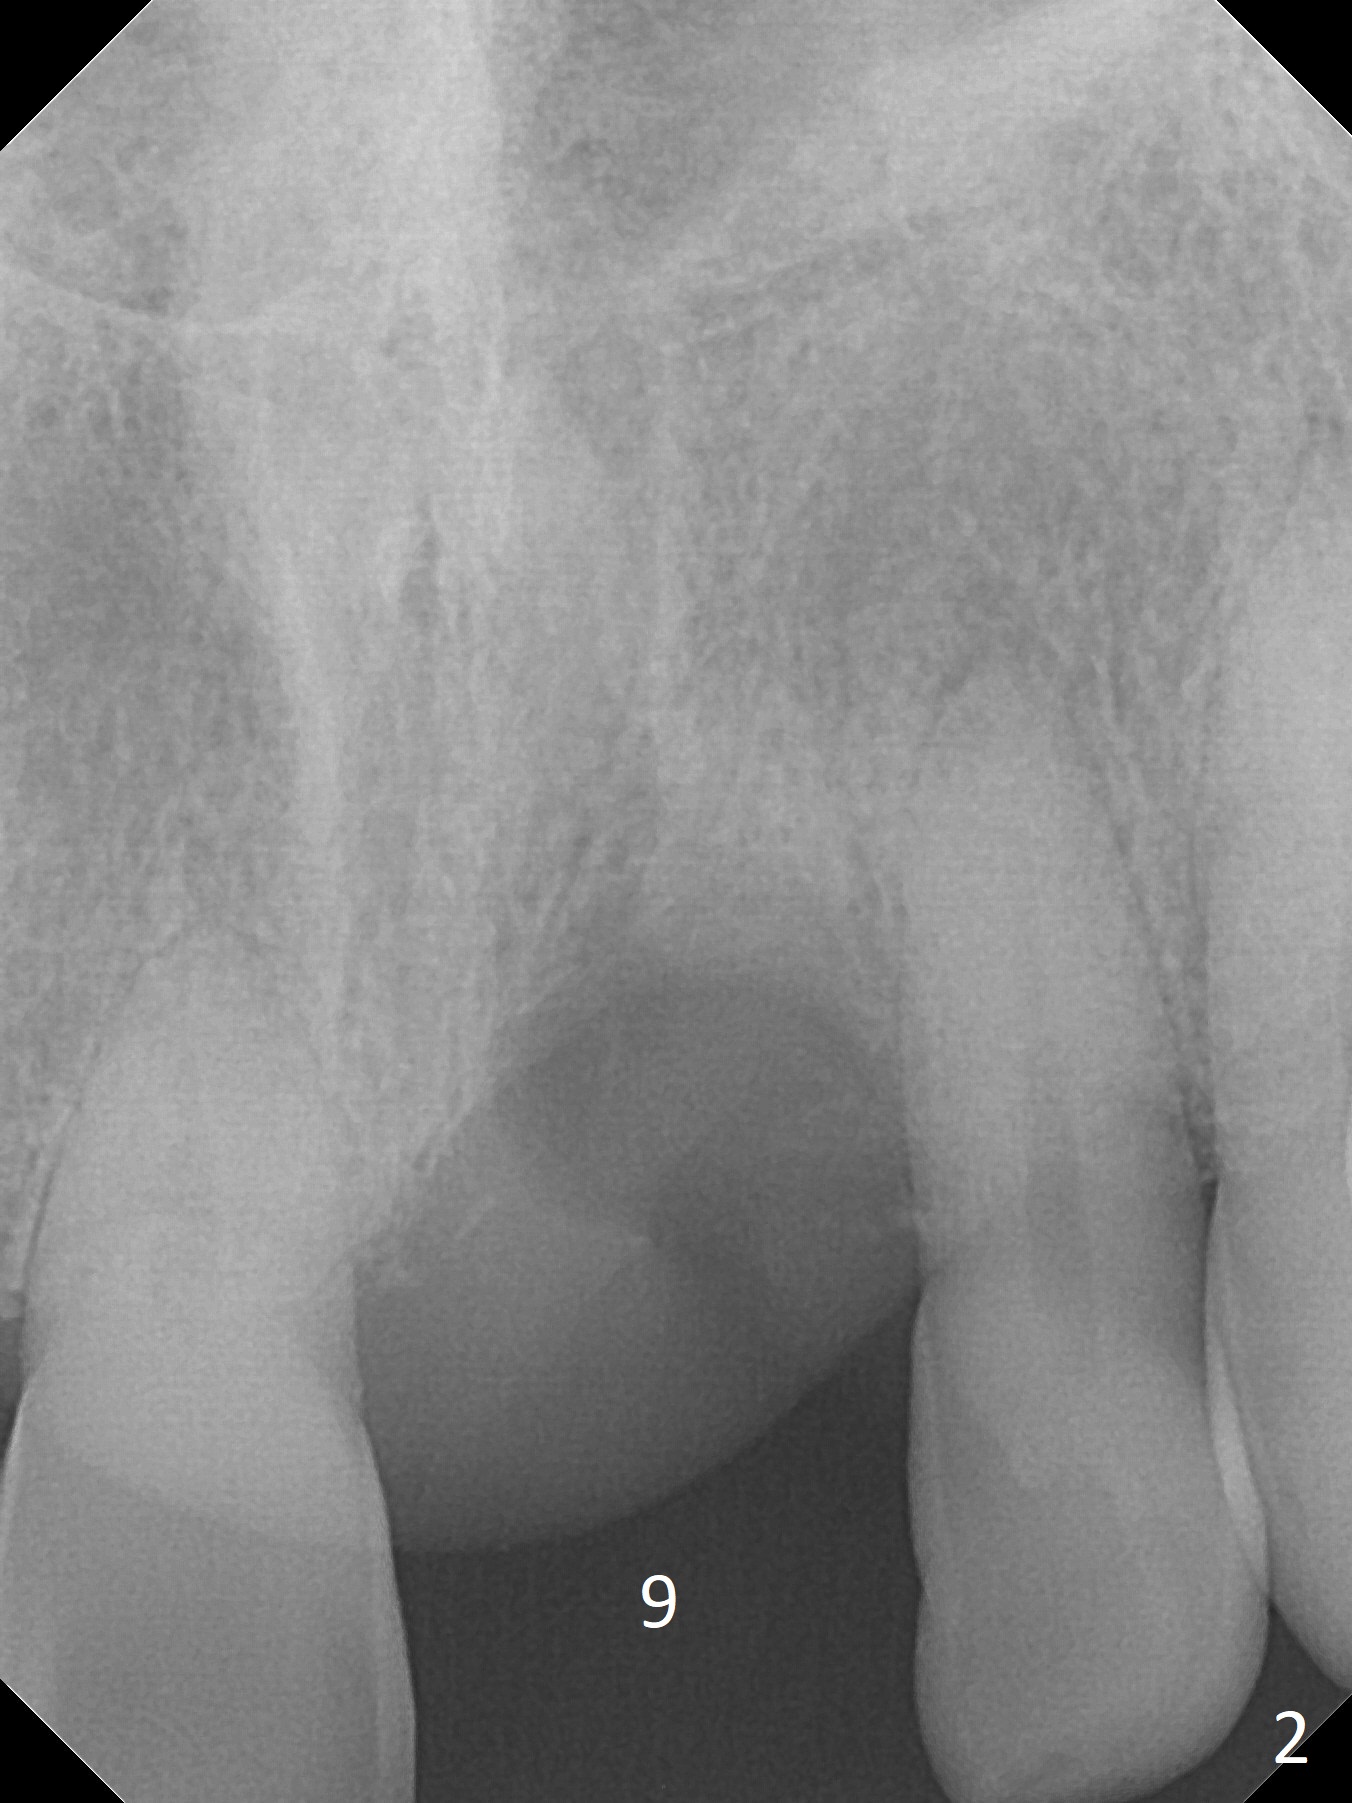

A 57-year-old man has lost the tooth #9 for 1-2 weeks (Fig.1,2). Although the buccal gingiva is recessive (cosmetically compromised), the middle and apical one thirds of the buccal plate appear to be minimally atrophic because of exostosis (Fig.1 *). An implant will be placed as palatal as possible (Fig.3). Use bone gauge to measure bone width. If the alveolus is atrophic, either use 3.5x13 mm implant or 1-piece (DIO or Tatum if there is a angulation problem). Prepare Planning Kit if IS implant is used. Adjust the opposing implant FPD, if needed.